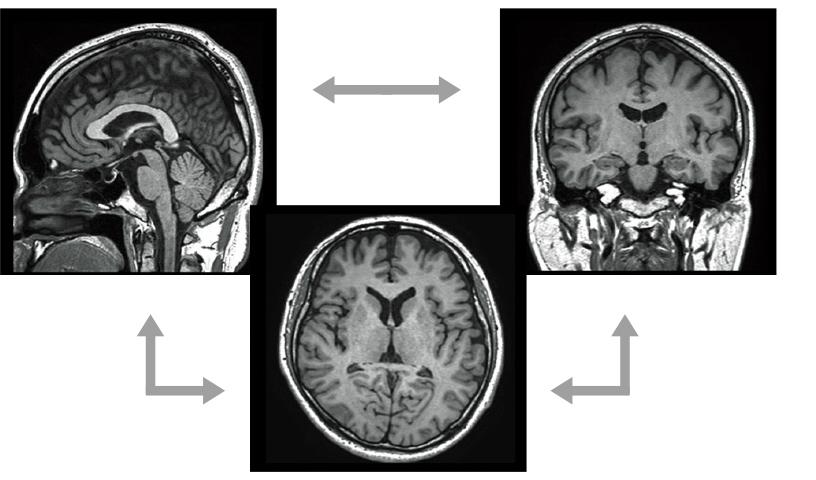

isoFSE

RF uygulama modellerinin optimizasyonuyla hayata geçen yüksek çözünürlüklü 3D görüntüleme

isoFSE, isovokseller için yüksek hızlı bir 3D görüntüleme işlevidir. FSE’nin yeniden netleme pulslarının çevirme açıları, MultiEchoes’un sinyal gücü dalgalanmalarından kaynaklanan etkiyi bastırmak ve yüksek çözünürlüklü 3D görüntüleme sağlamak için kullanılmaktadır. Bu uygulama modellerinin optimizasyonu, T1WI, T2WI ve FLAIR görüntüleri ile elde edilen yüksek kontrastlarla sonuçlanır.

Görüntülemede elde edilen yüksek uzamsal çözünürlüklü hacim verileri, MPR işlemede herhangi bir çapraz görüntülerini yeniden oluşturmak için kullanılabilir.Akıllı ÇALIŞMA